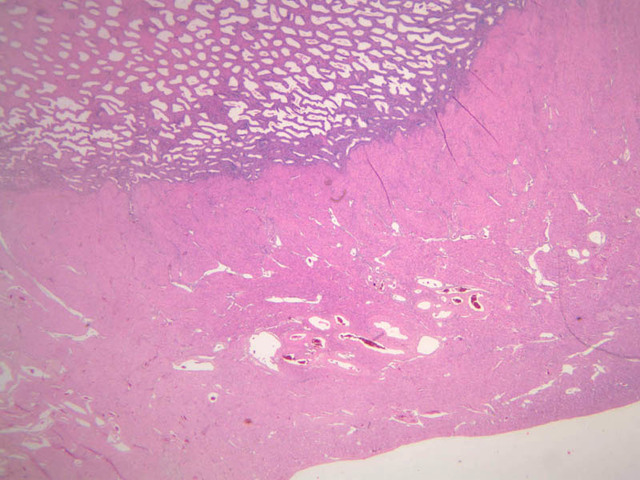

Mammary Gland

The resting or inactive mammary gland consists of predominantly dense connective tissue with small clusters of ducts and a few glandular elements (slide A-93 [2.5x-labeled, 10x, 20x, 40x] [1x, 2.5x, 10x, 20x]). It is difficult to differentiate between small ducts and alveoli as each is lined by simple low cuboidal cells. Lobes and lobules are not well defined. During puberty, predominantly under the influence of the ovarian hormone estrogen, the glandular or epithelial ducts proliferate and begin to differentiate into clusters of ductal and alveolar units termed terminal ductal lobule units (TDLUs). The non-pregnant gland will form multiple TDLUs that will not fully differentiate until pregnancy-induced growth. TDLUs are classified into Type I, Type II and Type III based on density of the ductules within each lobular unit. Type I and Type II lobules are typical of inactive glands that have not undergone a pregnancy cycle. Type III lobules are seen only in active glands or in inactive glands that have been through a pregnancy. Intralobular connective tissue is loose connective tissue that surrounds the alveoli and ducts within a lobule. The interlobular connective tissue is dense and contains considerable adipose tissue.

During pregnancy, predominantly under the influence of the ovarian hormone progesterone and the pituitary hormone prolactin, the glandular elements proliferate and differentiate to form milk-secreting units. In later stages of pregnancy, alveolar development becomes prominent and the amount of connective tissue and adipose tissue decreases. The secretory cells hypertrophy and accumulate secretory product.

The mammary gland in its active state is a compound tubuloalveolar gland (slide A-92 [10x, 20x, 40x-labeled] [2.5x, 10x, 20x, 40x]; A-94 [2.5x, 10x, 20x, 40x]). At this time, the gland is predominantly glandular tissue. Each alveolus is lined by a simple cuboidal epithelium. At the base of these cells, and within the alveolar basal lamina, are the stellate-shaped myoepithelial cells that are highly contractile and function to facilitate milk ejection.